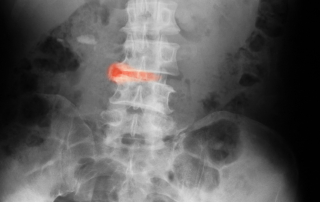

Sürekli sabah tutukluğu ile uyanıyorum diyorsanız DİKKAT ANKİLOZON SPONDİLİT olabilirsiniz.! Hastaların çoğu ilk olarak kronik